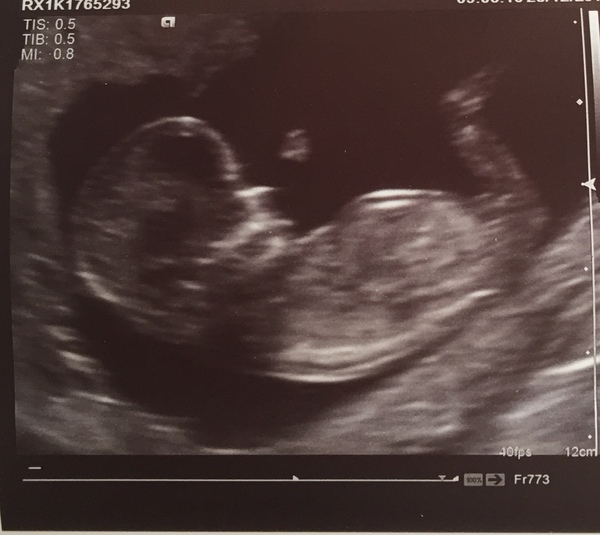

All good! 12 weeks 3 days, due 9th July! Can’t believe it’s happening! Good luck everyone for today x

@twistering congratulations on your lovely scan !

@twistering what a lovely scan photo! Congratulations 😍

Ah ha! I’m at work so I have just taken the kitchen bicarb and pot to the loo and it fizzed up like a pint lol a lovely head... I also did Chinese prediction saying boy and if you look at my scan there might be something there ... what do you recon.. I also have been fortunate enough to no suffer from morning sickness yet 14 + 1... lol

Chinks123 · 28/12/2018 15:28

@TwinkleDay I can see something on the scan, I can’t see the other leg though.. it might be that, otherwise it looks to be a boy Grin I’ve escaped morning sickness in both pregnancies (so far) too, but last one was a girl. Can’t wait till we all find out!

@twinkleday I don't think it'd be developed enough for that to be boy parts would it ? Maybe the cord ?